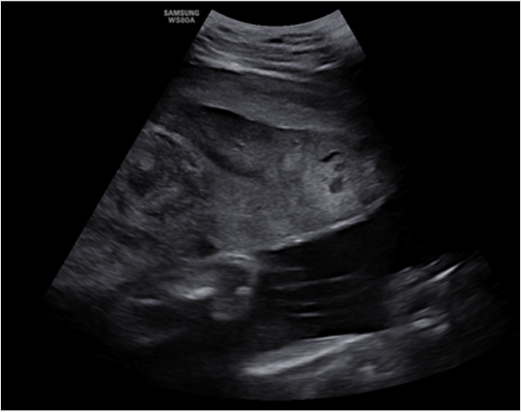

그림2. 태반조기박리. 자궁 후면의 혈종이 (화살표) 확인되나, 정상태반조직과의 감별이 어려움.

태반조기박리태반조기박리의 진단에 있어서 초음파의 활용도는 매우 제한적이다. 아주 심한 태반조기박리의 경우 초음파로 태반 후면의 혈종이 확인되나 대부분의 경우 태반 후면의 혈종과 정상태반조직의 감별이 어려워 초음파 단독으로는 진단이 어렵다. 임상적으로 다양한 증상이 있으나 갑자기 발생한 복통, 질출혈, 자궁 압통, 태아심박동 이상이 동반될 경우 태반조기박리를 의심할 수 있다. 위험요인으로 태반조기박리의 과거력, 고령산모, 다태임신, 고혈압, 저출새 체중아 등이 있으므로 임상증상과 병력을 고려한 진단이 필요하다.